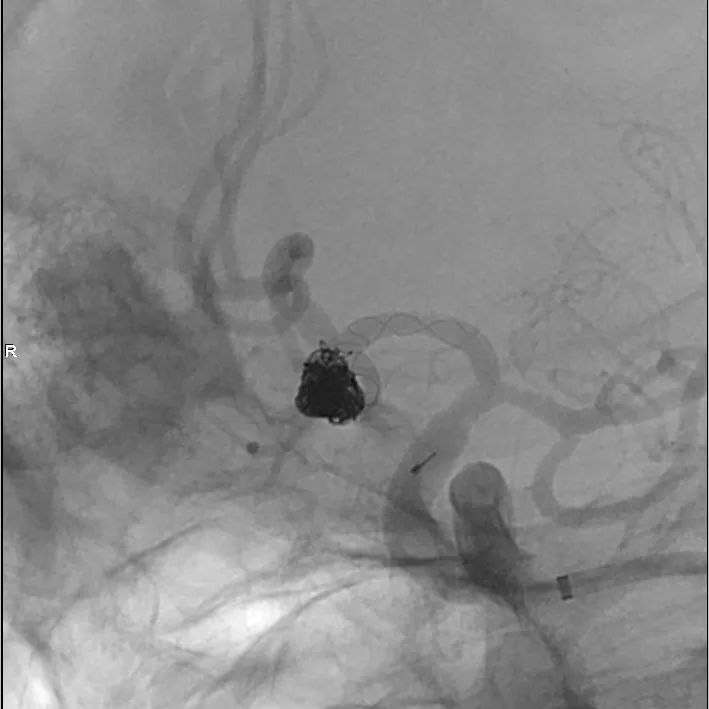

术毕,填塞满意。

动脉瘤填塞满意。

支架展开、贴壁良好,分支血管通畅。